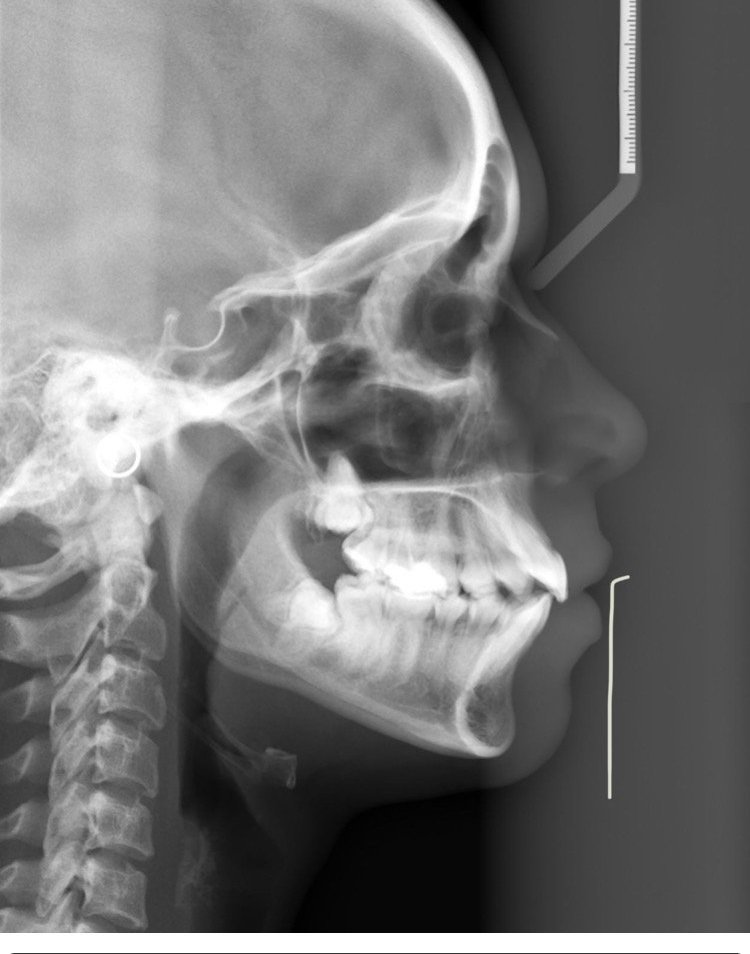

lanister,  аз съм в същото положение като твоето. И просто това ходене по мъките с мъдреците ме отказва изобщо да започвам процедурата с алайнери. Другото, което ме притеснява, че единия мъдрец е много близо до мандибуларния нерв, което ще рече, че трябва да попадна на много, много добър хирург стоматолог. Все още съм в прочуване за такъв в Пловдив.... И май ще си остана с криви зъби...

Момичета, имах панически страх от ваденето на мъдреците. Поревах си даже като ми казаха, че трябва да ги вадя, а не съм чак такава лигла по принцип. Обаче няма такова облекчение! Пет години от страх търпя болки в гърлото заради тези мъдреци, единия даже ми развали зъба, който бута и трябваше освен да вадя мъдреца, да умъртвя зъб. От напрежение пък от съседната страна зъб, който беше вече умъртвен и за коронка се пукна и трябваше да го извадя, та сега и имплант трябва да слагам. Повярвайте ми, тегавото е 1 час в кабинета и 3 дни след това, но после забравяте, че се е случило. За Пловдив препоръчвам д-р Стоянов в Дентален център 2. И двата ми долни зъба бяха до нервите точно, след 3д скенер опитен хирург ще се справи с ваденето. Не е задължително да сте с прави зъби, разбира се, но не бъдете като мен, можех да съм си спестила 300 главоболия до сега ако ги бях извадила преди 5 години, когато ми казаха.

Мен ме оперираха в София в медстом, др Мохамед и др Ондос, много опитни. Но един долен мъдрец си остана само с опита. Костта ми там е много тънка и има голям риск от счупване на долната челюст. Казаха ми, че ако се вади, трябва да е в болница с готовност за шиниране, ако ме счупят, после месец възстановяване. За късмет не расте в посока на другите зъби и започнах алайнерите. Но трябва да се прави 3д снимка да се види дали не е разбутал корена на съседния зъб. Та дано и да  не се наложи, но след като мина всички алайнери пак ще го гледаме, белким се отвори малко място там отзад. На мен ми е по-спокойно да ги няма мъдреците, и без това нямаше място къде да пораснат. Да си спестя болки в гърлото, подувания и тн. Но за умъртвяване на други здрави зъби много ми се свиди, то и като се разболее да ми умъртвят, се изяждам от яд. Засега само шести имам умъртвявани, та си личи, посивели, венеца пред тях смъкнат, пломби пак периодично се сменят, ужас... То умъртви ли се, се почва: смени на пломби, инфекции, коронки, мостове, съседни покрай него - след 10-20 години може и да го няма... Това здрав зъб да жертваш ептен не ми влиза в главата

На мен всички мъдреци са ми извадени. Горните ми растяха към бузите и ми правеха рани. А долните бяха ретинирани обаче растящи под венеца хоризонтално къв 7мите зъби. Не стига, че ми разбутаха редиците правилно подредени зъби, ами и двата ми долни шести зъба са с коронки и умъртвени най-вероятно от натиска. Защото бяха чисто бели зъби дори при пробиване просто азведнйж имах силна болка и нурва е умрял уж безпричинно. А те натискаха точно огдолу корените на др зъби.